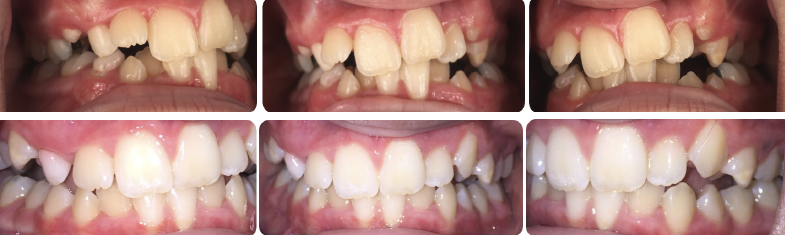

Fig 3. Pretreatment (top panels) and peri-treatment (bottom panels) intraoral photographs.

Figure 3